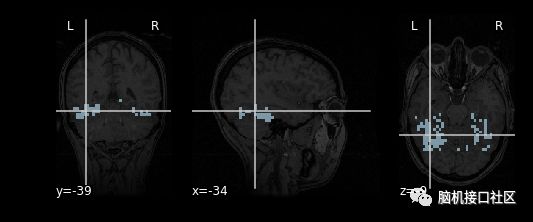

以受检者的解剖图像为背景对其进行可视化

"""

mask_filename = haxby_dataset.mask_vt[0]

from nilearn import plotting

plotting.plot_roi(mask_filename, bg_img=haxby_dataset.anat[0],

cmap='Paired')